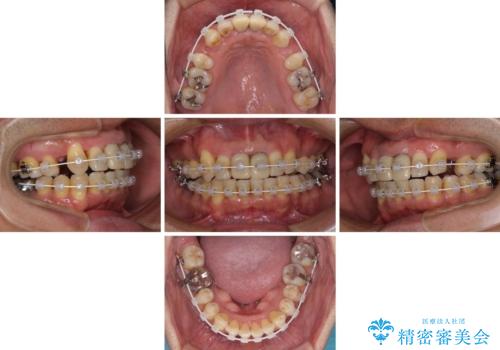

- 矯正装置

- 審美装置

- 治療期間

- 2年6ヶ月

- 治療回数

- 30回以上